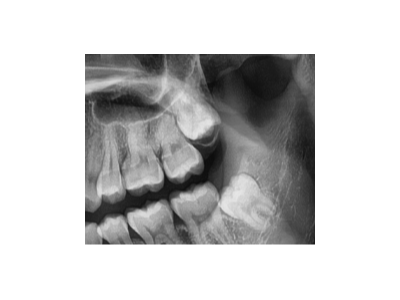

種植牙是一種常見的牙齒修復(fù)方式,術(shù)前準(zhǔn)備對(duì)于手術(shù)的成功和術(shù)后恢復(fù)至關(guān)重要。以下是種植牙術(shù)前的主要準(zhǔn)備工作:一、全面口腔檢查與評(píng)估口腔檢查:包括牙齒、牙齦、咬合關(guān)系、頜骨狀況等。影像學(xué)檢查:全景片(曲面…